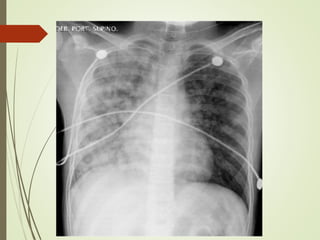

 Chest xray

 Butterfly appearance

 Kerley B lines

 Pleural effusion

 alveolar edema and interstitial edema

Laboratory Investigations  Routine;CBC  Liver function tests  Renal Function Tests  Arterial blood gas analysis  Serum cardiac biomarkers  Chest xray  Butterfly appearance  Kerley B lines  Pleural effusion  alveolar edema and interstitial edema